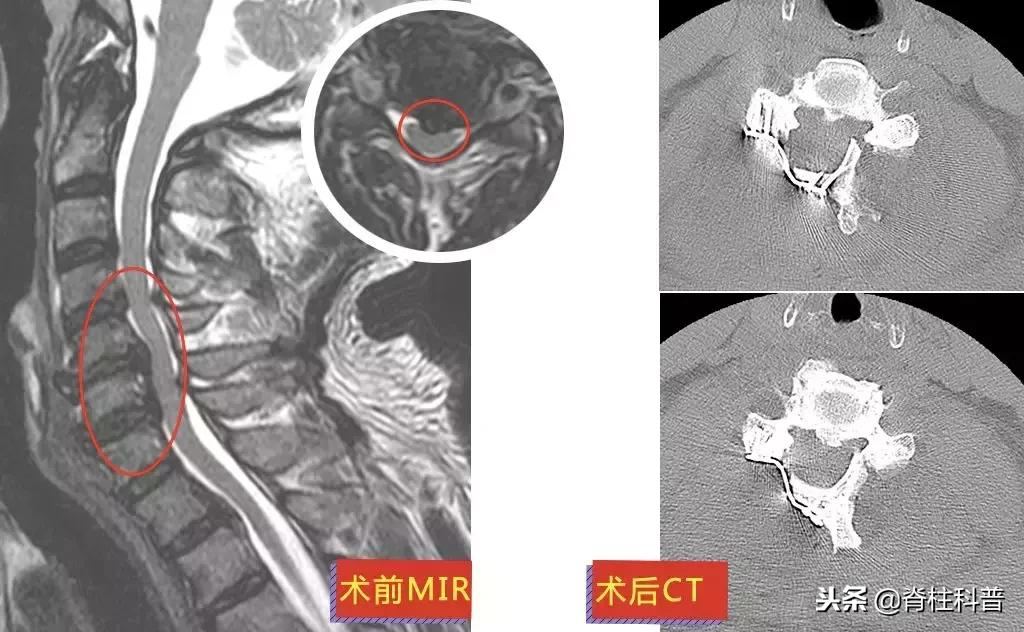

廖四爷(化名)4年前第一次发病:右上肢刮骨样疼痛和乏力。而后的每一次发病,他都只接受牵引等保守治疗,长达4年。可保守治疗的效果逐渐减退。2018年8月23日前来就诊时,廖四爷的右上肢上臂已经出现肌肉萎缩。

▲ 廖四爷:术前MRI与术后X光

11月26日,在张主任的门诊,廖四爷回来复诊。情况还不错,上肢刀割样的疼痛已经消失,照了CT内固定也长得很好,但是萎缩的手臂还没得到恢复,还需要接受康复治疗。